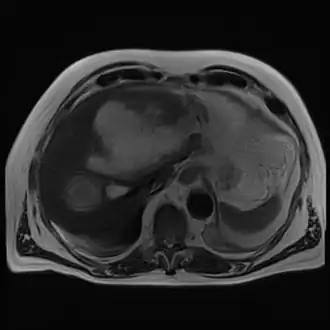

Magnetic resonance cholangiopancreatography (MRC) image showing a voluminous and heterogeneous collection in the left liver lobe (amoebic abscess)

Magnetic resonance cholangiopancreatography (MRC) image showing a voluminous and heterogeneous collection in the left liver lobe (amoebic abscess)